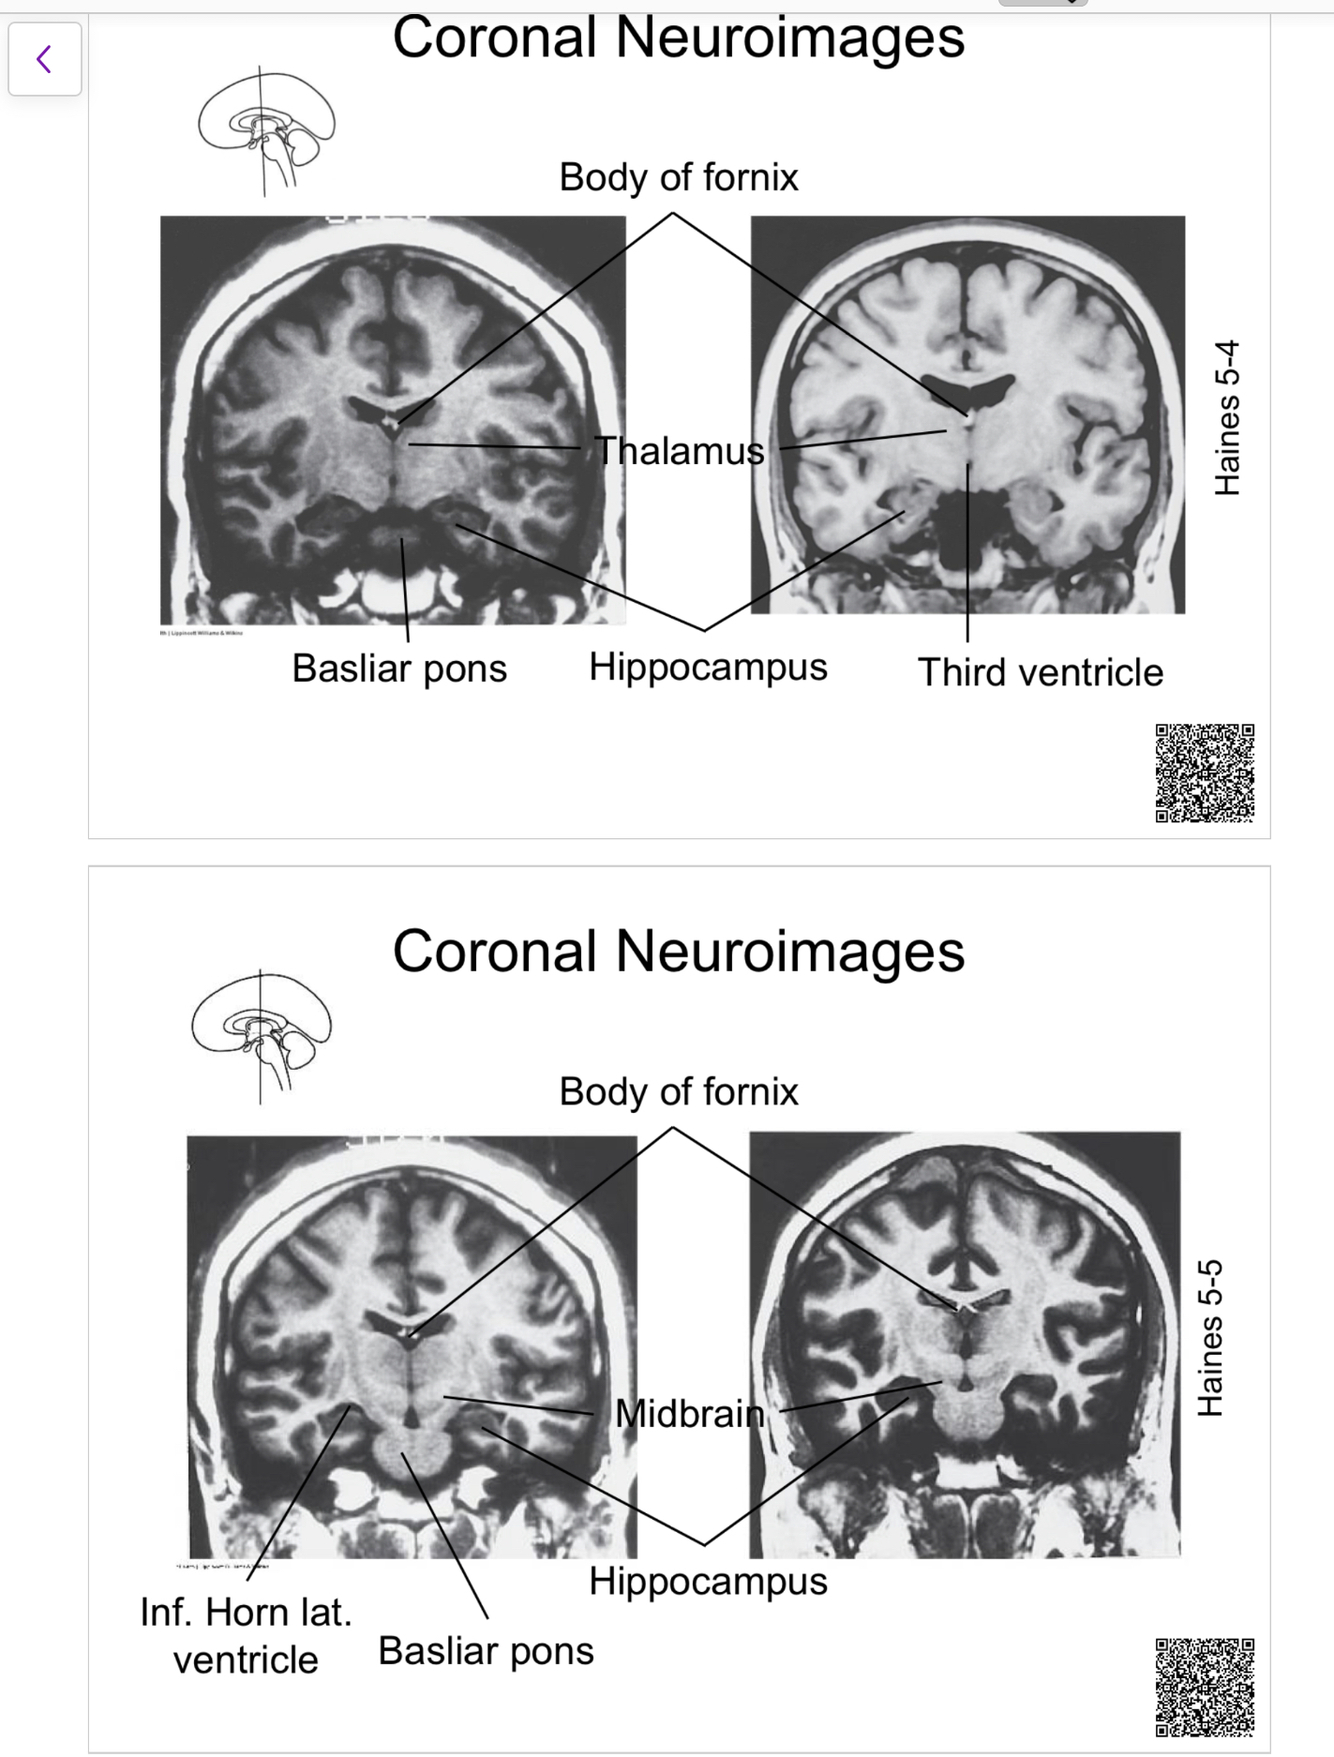

The structure indicated by the red line is?

other format too much work….